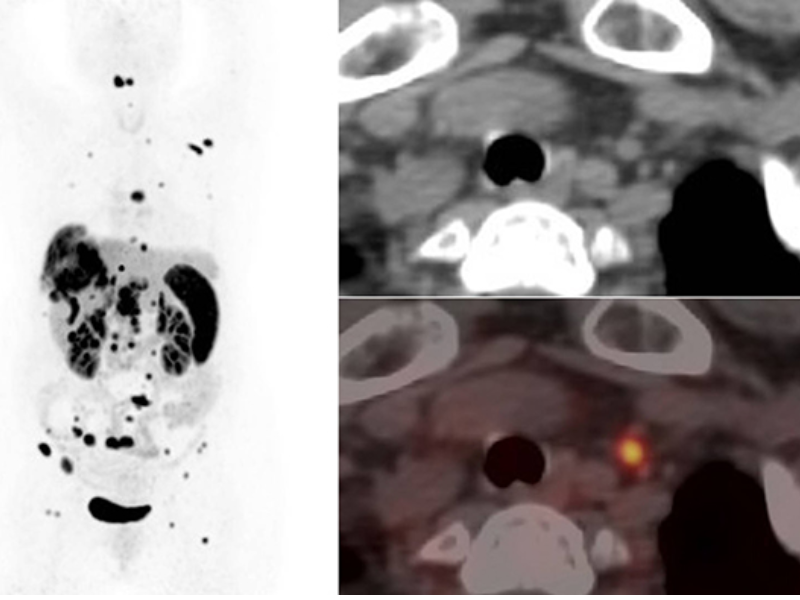

Small Lesions Detectability with Gallium-68